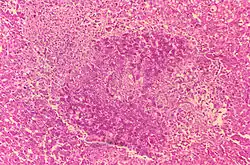

- Histologic evidence of granulomatous hepatitis on hepatic biopsy